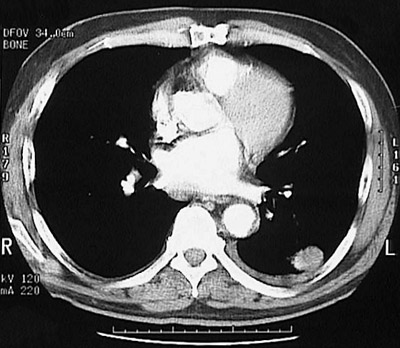

This chest CT scan at "soft tissue window" density reveals a peripheral mass that on CT guided biopsy was found to be an adenocarcinoma.